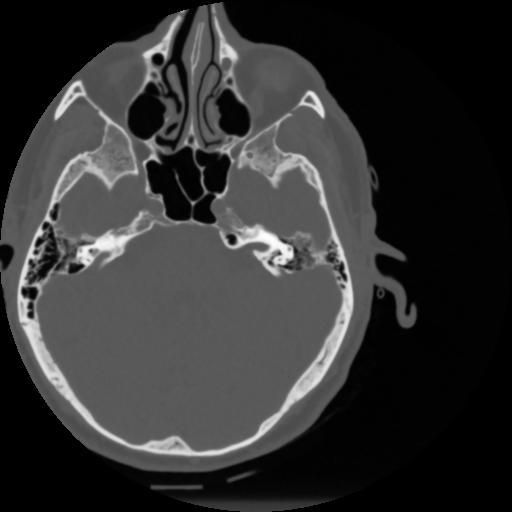

4 CEREBRO,,Vol,0.5,CEREBRO,,